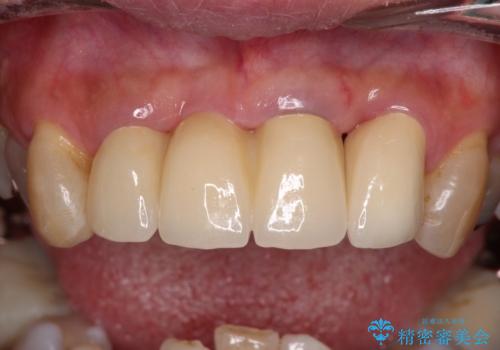

また、前歯に抜歯が必要な歯があったため、抜歯をし、傷の治りを待ってオールセラミックブリッジにて補綴治療を行うこととしました。

一番気になっていた隙間が埋まり、不快感から解放されました。